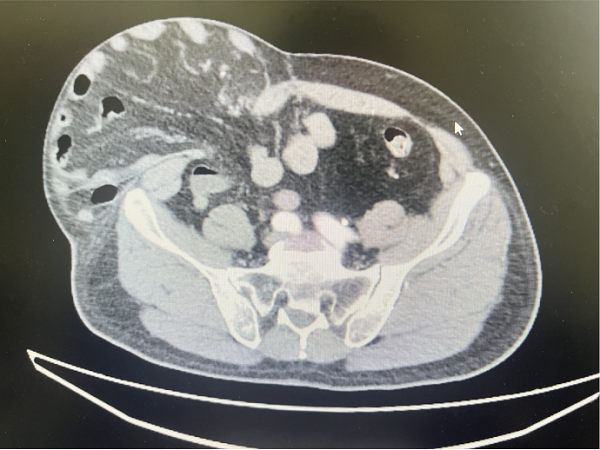

五、胃肠外科:术后并发症巧修复,精准施治解疾苦

1.腹壁切口疝无张力修补术:王林财主治医师、宋晨主治医师为一名61岁男性患者实施腹壁切口疝无张力修补术。该患者4年前于我院行直肠癌根治术,术后因年龄相关腹壁组织退行性变及长期腹压增高,出现腹部切口处可复性包块且逐渐增大3年余。手术在腰麻下进行,术中见腹壁肌层及筋膜层缺损,团队分离疝囊后回纳内容物,采用补片行无张力修补并留置引流管,手术过程顺利,患者目前恢复良好。切口疝是腹部手术常见远期并发症,无张力补片修补术为其首选治疗方式,可有效降低复发率,改善患者生活质量。